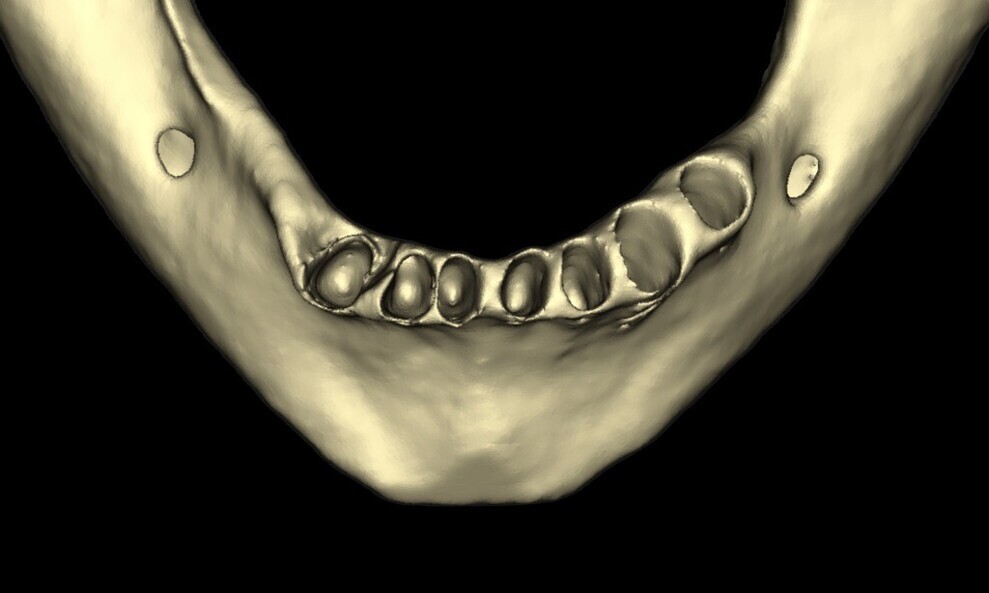

A CBCT scan was taken to determine the quality and quantity of the bone in the edentulous areas. The radiographic analysis showed adequate bone height in the areas of tooth extraction, allowing for immediate implant placement. The remaining bone provided sufficient support for initial stability during implant placement. Sufficient horizontal ridge width was observed in the potential implant sites, ensuring proper implant positioning without the need for additional ridge augmentation. Bone quality was favourable for immediate implant placement. The anterior maxilla presented moderate to good bone density (Type II–III) and the mandible excellent bone density (Type I–II), particularly in the posterior regions, indicating high primary stability for implants. Subsequently, digital impressions were obtained using the TRIOS intra-oral scanner (3Shape) and exported in STL file format (Figs. 8 & 9).

Figs. 11–15: DICOM files, STL files and clinical photographs were integrated into Smilecloud, leveraging artificial intelligence for precise, personalised smile design.

To ensure precise and predictable treatment planning, the DICOM files, STL files and clinical photographs were seamlessly integrated into Smilecloud, utilising advanced artificial intelligence technologies to deliver a highly personalised smile with exceptional precision (Figs. 11–15).